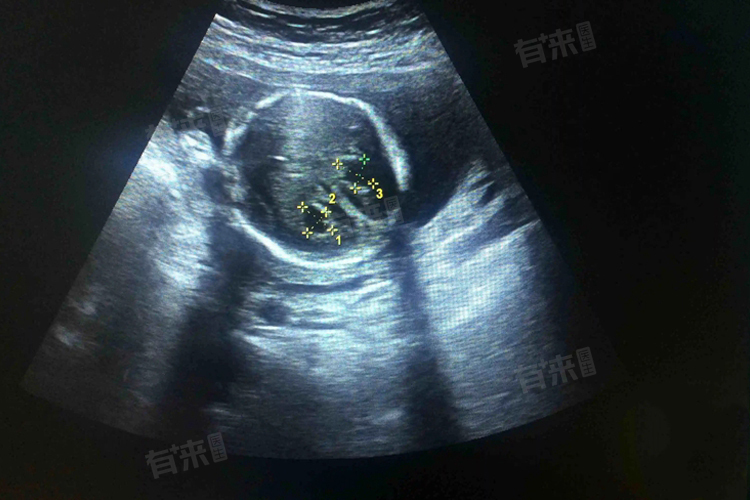

3、病情诊断:对于胎儿期的脉络丛囊肿,通常在产前超声检查中被发现。超声可以显示囊肿的位置、大小、形态等,在成人中,头颅磁共振成像是常用的检查方法,可以更清晰地显示脉络丛囊肿的特征以及与周围组织的关系。